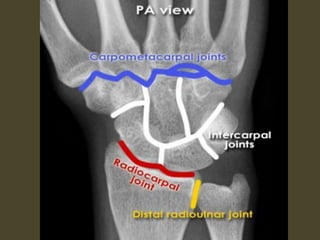

Wrist X-ray Anatomy.